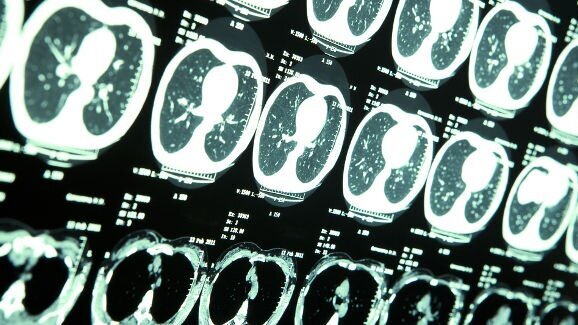

TAIPEI, Taïwan : Des études antérieures ont suggéré que les dépistages radiographiques dentaires et médicaux fréquents sont associés au maximum à un risque multiplié par 5 d’apparition de tumeurs cérébrales bénignes. Toutefois, une récente étude menée par des chercheurs taiwanais a conclu qu´il n’y a pas d’association entre des tumeurs cérébrales malignes et les radiographies dentaires.

Les chercheurs ont réalisé deux études afin d'évaluer le risque de développer des tumeurs malignes du cerveau, en fonction de la fréquence des radiographies dentaires reçues lors de soins bucco-dentaires ou maxillo-faciaux. La première étude portait sur 4.123 patients atteints de tumeurs cérébrales bénignes et 16.492 témoins sains, tandis que la seconde étude a été menée auprès de 197 personnes atteintes de tumeurs cérébrales malignes et 788 contrôles.

L’analyse des données des patients a démontré que le risque de tumeurs cérébrales bénignes augmentait avec la fréquence des radiographies dentaires. Cependant, aucune association significative n’a été trouvée entre les tumeurs cérébrales malignes et l’exposition au rayons x lors de radiographies de diagnostic dentaire.

L'étude a été menée à l'Université de Médecine de Chine à Taichung, en collaboration avec plusieurs autres institutions scientifiques de la santé dans tout l´archipel. Selon l'Association américaine des tumeurs cérébrales, environ 69 720 nouveaux cas de tumeurs primaires du cerveau devraient être diagnostiqués en 2013 aux États-Unis, y compris des tumeurs malignes (24 620) et des tumeurs bénignes de cerveau (45 100). Les méningiomes, qui sont principalement des tumeurs cérébrales bénignes, représentent 34 % de toutes les tumeurs primaires du cerveau et constituent les tumeurs cérébrales primaires les plus courantes.

L'étude a été publiée en ligne le 13 février dans le journal Annals of Oncology avant impression.